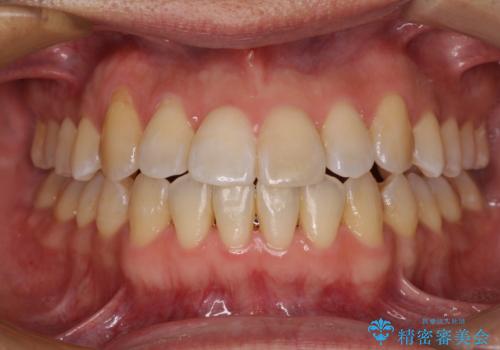

[ 前歯開咬 ] 前歯が噛んでいない マウスピース矯正治療

担当医 大元洋佑

![[ 前歯開咬 ] 前歯が噛んでいない マウスピース矯正治療の症例 治療後](https://seimitsushinbi.jp/wp/wp-content/uploads/2022/11/IMG_2488-500x350.jpg?v=1668218373)